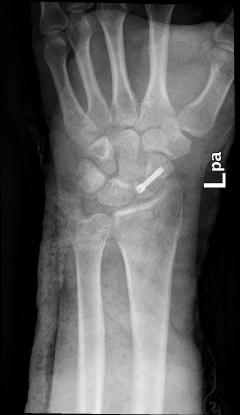

Τα περισσότερα κατάγματα σκαφοειδούς μπορεί να αντιμετωπιστούν επιτυχώς χωρίς χειρουργική επέμβαση. Αυτό όμως συνεπάγεται γύψινη ακινητοποίηση από 8 εβδομάδες έως και 6 μήνες. Γι’ αυτό η τρέχουσα τάση είναι να χειρουργούνται, εκτός εάν συντρέχουν λόγοι που αποτρέπουν αυτή την απόφαση. Χρησιμοποείται ειδικά σχεδιασμένες βίδες ή βελόνες. Με τον τρόπο αυτό αποφεύγεται η χρήση γύψου, ο ασθενής επιστρέφει ταχύτερα στην εργασία του και οι επιπλοκές περιορίζονται σημαντικά.

Χρησιμοποιώ τεχνικές ελάχιστης παρέμβασης (Μinimal Ιnvasive Surgery), όπως και άλλοι χειρουργοί χειρός διεθνώς. Η επέμβαση γίνεται μέσω μιας τομής 1 εκατοστού, υπό διεγχειρητικό ακτινοσκοπικό έλεγχο. Το διεγχειρητικό τραύμα ελάχιστο, δεν χρειάζεται μετεγχειρητική ακινητοποίηση και η πώρωση είναι ταχύτερη, καθώς δεν έχει επηρεαστεί περαιτέρω η αιμάτωση του σκαφοειδούς.